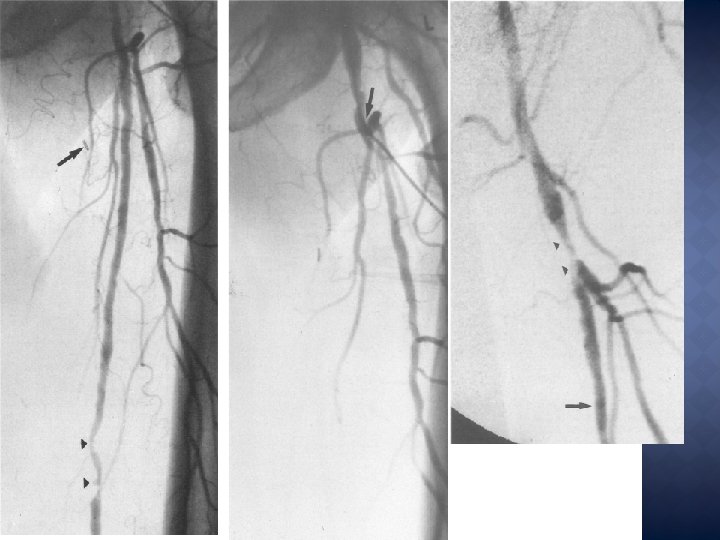

� FAUX • • • - ANEVRYSMES: 0, 6 à 6 % des cathéterisations fémorales FDR: Anticoagulants – Largeur de l’intro – HTA – Obésité – faute technique lors de la ponction – Compression manuelle inadaptée – sexe féminin – hémodialyse Les petits FA (< 3 cm) se thrombosent souvent spontanément et sont suivis par écho Indication traitement: evolutivité – douleur – rupture – ischémie cutanée – neuropathie de compression – embolisation distale

� FISTULES • • - ARTERIO VEINEUSES Souvent liées à une ponction simultanée A+V Kelm et Perings 2002: FAV chez 88 / 10, 000 KT cardiaque FDR: Anticoagulants HTA Sexe féminin Ponction gauche La ponction AFP/AFS augmente le risque de FAV Leur effet délétère extrêmement rare

� Délai de présentation plus long (4, 5 jours moy) � Claudication / Douleurs de décubitus � Thrombose au point de ponction � Sténose au point de ponction : dissection localisée pouvant se réaccoler en qques jours ou évoluer � Rôle pointé des DFV